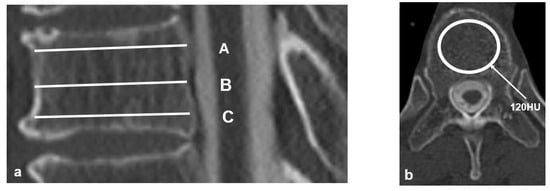

The HU values were evaluated at three points for each vertebral body as follows: immediately inferior to the superior endplate (Figure 1; line A), middle of the vertebral body (Figure 1; line B), and immediately superior to the inferior endplate (Figure 1; line C). These three values were then averaged for each individual vertebral body (Figure 1). The UIV fractures were evaluated on the basis of a semiquantitative (SQ) technique, which used a standard CT scan, and was graded on visual as follows: normal (grade 0), mildly deformed (grade 1, approximately 20–25% reduction in anterior, middle, and/or posterior height and a reduction in area 10–20%), moderately deformed (grade 2, approximately 25–40% reduction in any height and a reduction in area 20–40%), and severely deformed (grade 3, approximately 40% reduction in any height and area) [30]. We examined age, sex, teriparatide usage, BMD measured on DXA scans, HU, and SQ grade as patients’ factors and UIV region (UT: upper thoracic, T1–T6, LT: lower thoracic, T7–T12), iliac fixation, and UIV fixation as surgery-related factors. Moreover, we examined TK, LL, PI, PT, SVA, and PJA as radiographic parameters.

Figure 1. Technique for obtaining Hounsfield units (HU) values. (a) Three HU measurements were evaluated as follows: (A) immediately inferior to the superior end plate; (B) middle of the vertebral body; and (C) immediately superior to the inferior end plate. (b) The oval pattern indicates an elliptical region of interest (ROI), which evaluates HU values on an axial image avoiding cortical bone.